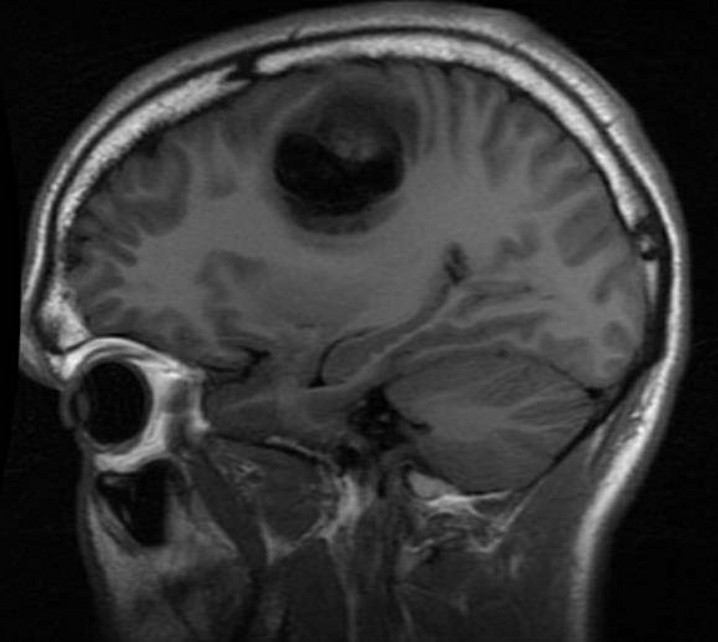

I’m a 17-year glioblastoma brain cancer survivor. I suffered greatly during cancer treatment and If I knew then what I know now, I would have used hemp-based products to find relief from the side effects of radiation and chemotherapy. Cancer patients are increasingly purchasing hemp products but the costs are high. I created the nonprofit so we can overcome that barrier and learn more in the process through case studies.